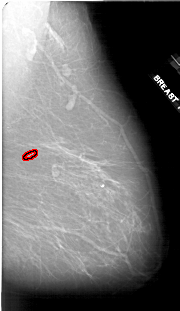

A_1910_1.LEFT_CC

LEFT_CC LINES 6556 PIXELS_PER_LINE 3751 BITS_PER_PIXEL 12 RESOLUTION 43.5 NON_OVERLAY

FILE: A_1910_1.RIGHT_CC.OVERLAY

TOTAL_ABNORMALITIES 1

ABNORMALITY 1

LESION_TYPE CALCIFICATION TYPE PLEOMORPHIC DISTRIBUTION CLUSTERED

ASSESSMENT 4

SUBTLETY 3

PATHOLOGY BENIGN

TOTAL_OUTLINES 1

BOUNDARY